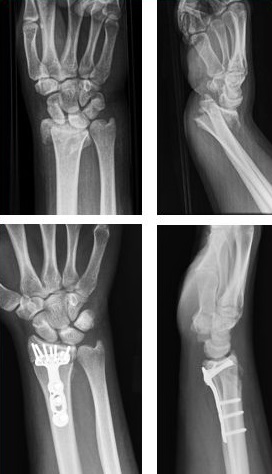

Upload Date: March 31, 2019 Full Size Image Dimensions: 272 × 474 Image Parent Post: Κατάγματα άνω άκρου

6.Εσωτερική οστεοσύνθεση κατάγματος κάτω πέρατος κερκίδας